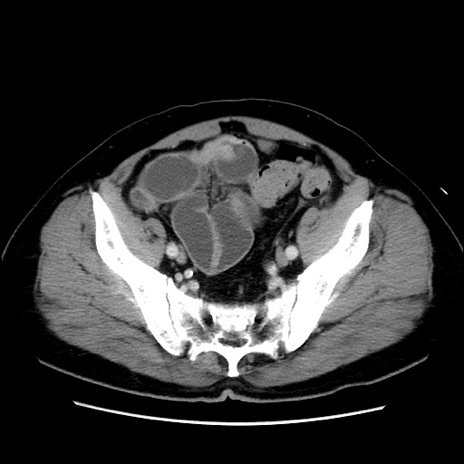

症例16(横断像)

【症例】 70歳代男性

【主訴】 腹痛、嘔吐

【現病歴】 約1ヶ月前より間欠的に腹痛と嘔吐あり、当院消化器内科を受診したところCTで多発する肝臓のLDAを指摘され、精査中であった。以降は消化器症状は安定していたが、2日前より嘔気と腹痛があり、同日より排便・排ガスが消失した。改善認めず、 本日、救急外来を受診した。

【既往歴】 大腸ポリープ切除後。

【身体所見】意識清明・会話良好、BT 36.3℃、BP 127/80mmHg、 P 80bpm、腹部:膨満あり、平坦・軟、上腹部正中および下腹部正中に圧痛あり、反跳痛なし、筋性防御なし。

【データ】WBC 7200、CRP 0.77